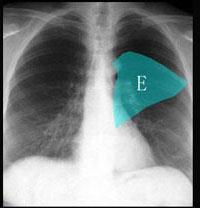

问题 在图所示正常胸部X线影像图像上,该英文字母所代表的肺段为 ( )

选项 A、后基底段 B、背段 C、前基底段 D、外基底段 E、内基底段

答案 B